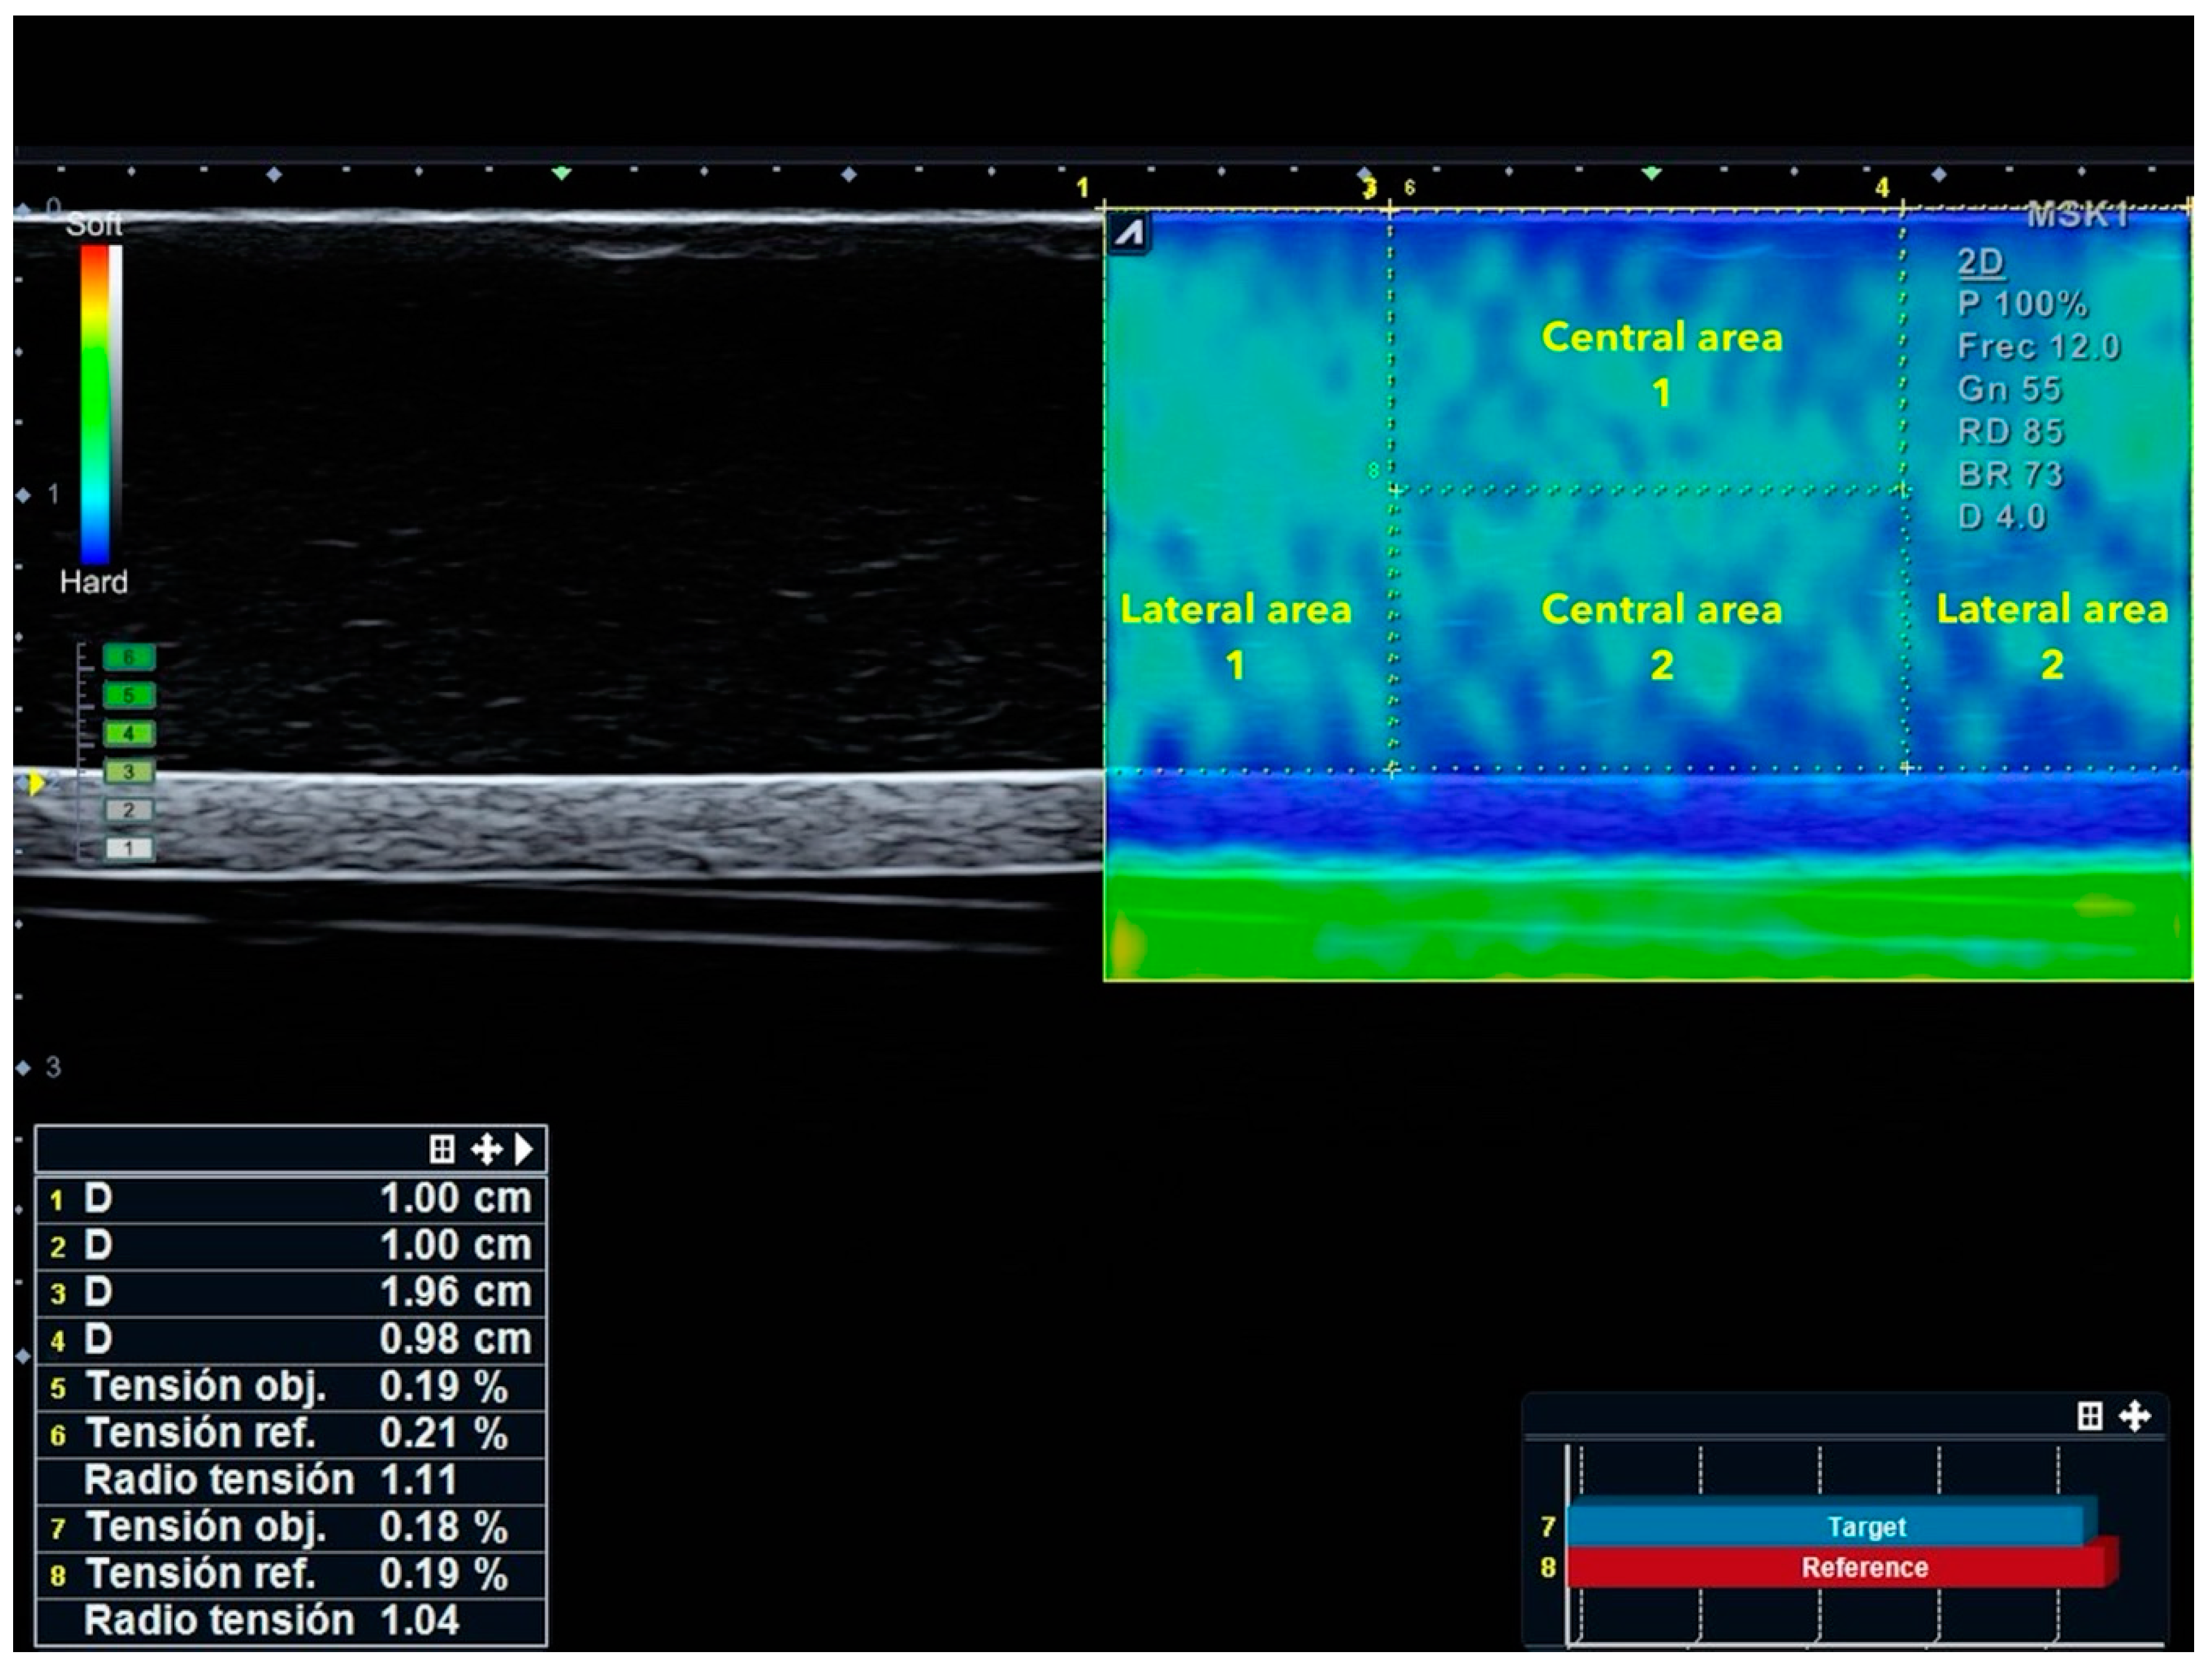

- Lateral areas of the image: First, the caliper was used to measure 1 cm from the top right corner of the image to the left. Then the area selector tool was utilized to contour a rectangle with 1 cm width and a height equal to the distance between the most superficial limit of the phantom to the most superficial limit of the cylindrical structure. Finally, another rectangle with same measurements (height and width) was placed in the top left corner of the image to obtain the SR.

- Central areas of the image: Within the central 2 cm that were not included in the previous measurement, the distance from the surface of the phantom and the upper limit of the cylindrical structure was divided by 2. Following this, a rectangle was contoured with a width of 2 cm and the upper half of the distance previously calculated from the surface to the fake vessel. Finally, the SR between the upper rectangle and the lower rectangle was calculated.